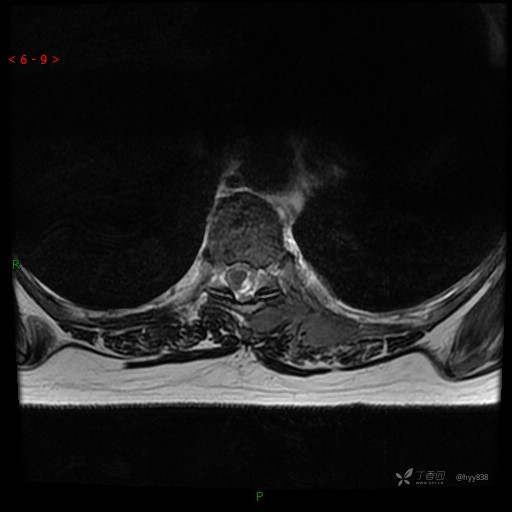

MRI AXI T2WI